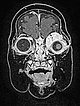

Coronal plane of T1-weighted MRI without contrast shows the mass homogeneously hypointense. Centrally, a few small flow voids visible, caused by strongly perfused arterial vessels.

T1-weighted, coronal MRI after contrast depicts a homogeneous, strong enhancement in a solid, sharply demarcated tumor of the left eye. This is suggestive of an infantile hemangioma as part of the spectrum of vascular tumors.

T1-weighted coronal plane MRI after contrast administration in a slightly more dorsal plane shows extension of the contrast-enhancing solid mass well into the medial orbit of the left eye with displacement of the eyeball caudally and laterally.